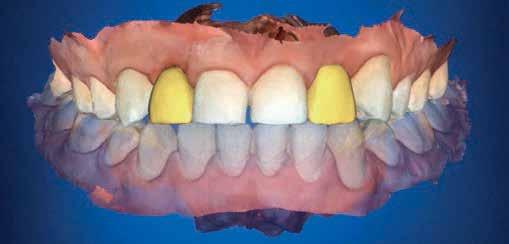

A bench scan (Medit T-710 Tabletop Scanner) of the cast and preoperative CBCT (3D Accuitomo 170) was made for each participant for the construction of a CAD CAM surgical guide. The implant was planned to engage the palatal wall, avoid pressure on the labial plate of the bone, and be 1-mm apical to the crest. A fully guided tooth-supported surgical guide was designed and then printed in clear acrylic resin (Dental SG Resin; Formlabs) by using a 3D printer (Form2; Formlabs). (fig 2)

The prosthetic procedures for definitive restorations were performed 3 months after implant placement. The healing abutment was removed (Fig 10) scan body was placed in position and a digital implant-level impression was made using an intraoral scanner (Medit I 700 3D scanners) (16) (Fig 11,12)

Exocad was used to design the restoration (fig. 13) and was milled from a super translucent multilayered zirconia (KATANA Zirconia STML; Kuraray Noritake). The milled restoration was cemented on the Ti-base with a resin cement (RelyX Unicem; 3M ESPE). Then, the definitive restoration was connected to the implant, and the Ti-base screw was tightened to 20 Ncm according to the manufacturer’s instructions. The screw access channel was sealed with sterilized PTFE and photopolymerized composite resin (Filtek Supreme Ultra; 3M ESPE). The definitive restoration was evaluated for centric and eccentric occlusal contacts and then finished and polished (fig 14,15).